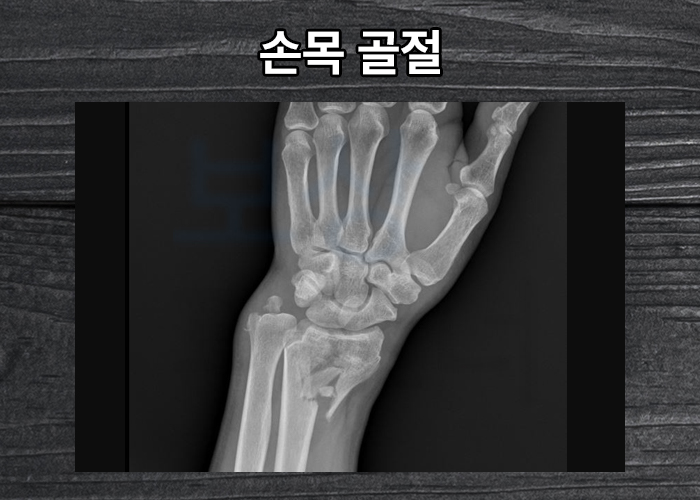

손목골절로 수술하신 김@@님이 산재처리 중 장해보상은 어떻게 받아야 하는지 문의해주셨습니다. 미리 전화해주셔서 함께 진행한 덕분에 김@@님은** 산재 장해등급 12급** 인정받을 수 있었는데요, 어떻게 보상 받았는지 오늘의 포스팅에서 소개해드리겠습니다.

김@@님은 크레인 자재 인양작업을 하시던 중 크레인에 손목을 부딪히는 사고를 당하셨는데요, 상기 사고로 김@@은

위 엑스선상에서 볼 수 있듯이 손목의 골절이 여러 골편으로 나뉘는 심각한 상태에 있게 되었습니다. 원래의 위치로 회복하고 금속으로 고정하는 관혈적 정복 및 금속고정술 받으셨는데요,

여러분들의 손목도 위 사진처럼 금속으로 고정해둔 상황일까요? 보상파트너의 산재노무팀은 노무직원과 환자와 직접 상담을 도와드리며** 구체적인 보상 과정과 가능성**을 설명해드렸습니다.

상기 사고로 관절면의 손상이 커 손목의 움직임이 원활하지 않을 수 있었습니다.